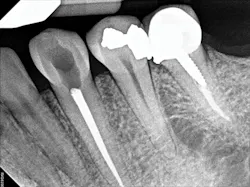

Figure 4: A periapical radiograph showing a partial view of the completed root canal therapy on tooth No. 22